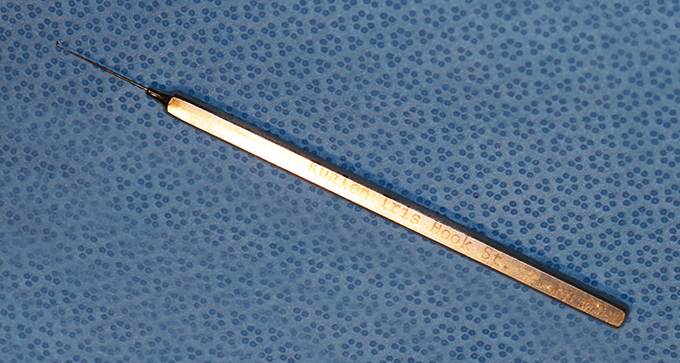

Kuglen Hook, angled, round handle

Angled Kuglen

Catalog: Katena K3-5523

Typical Use(s): Position IOL and haptics; Fix eye with paracentesis; Retrieve suture from AC